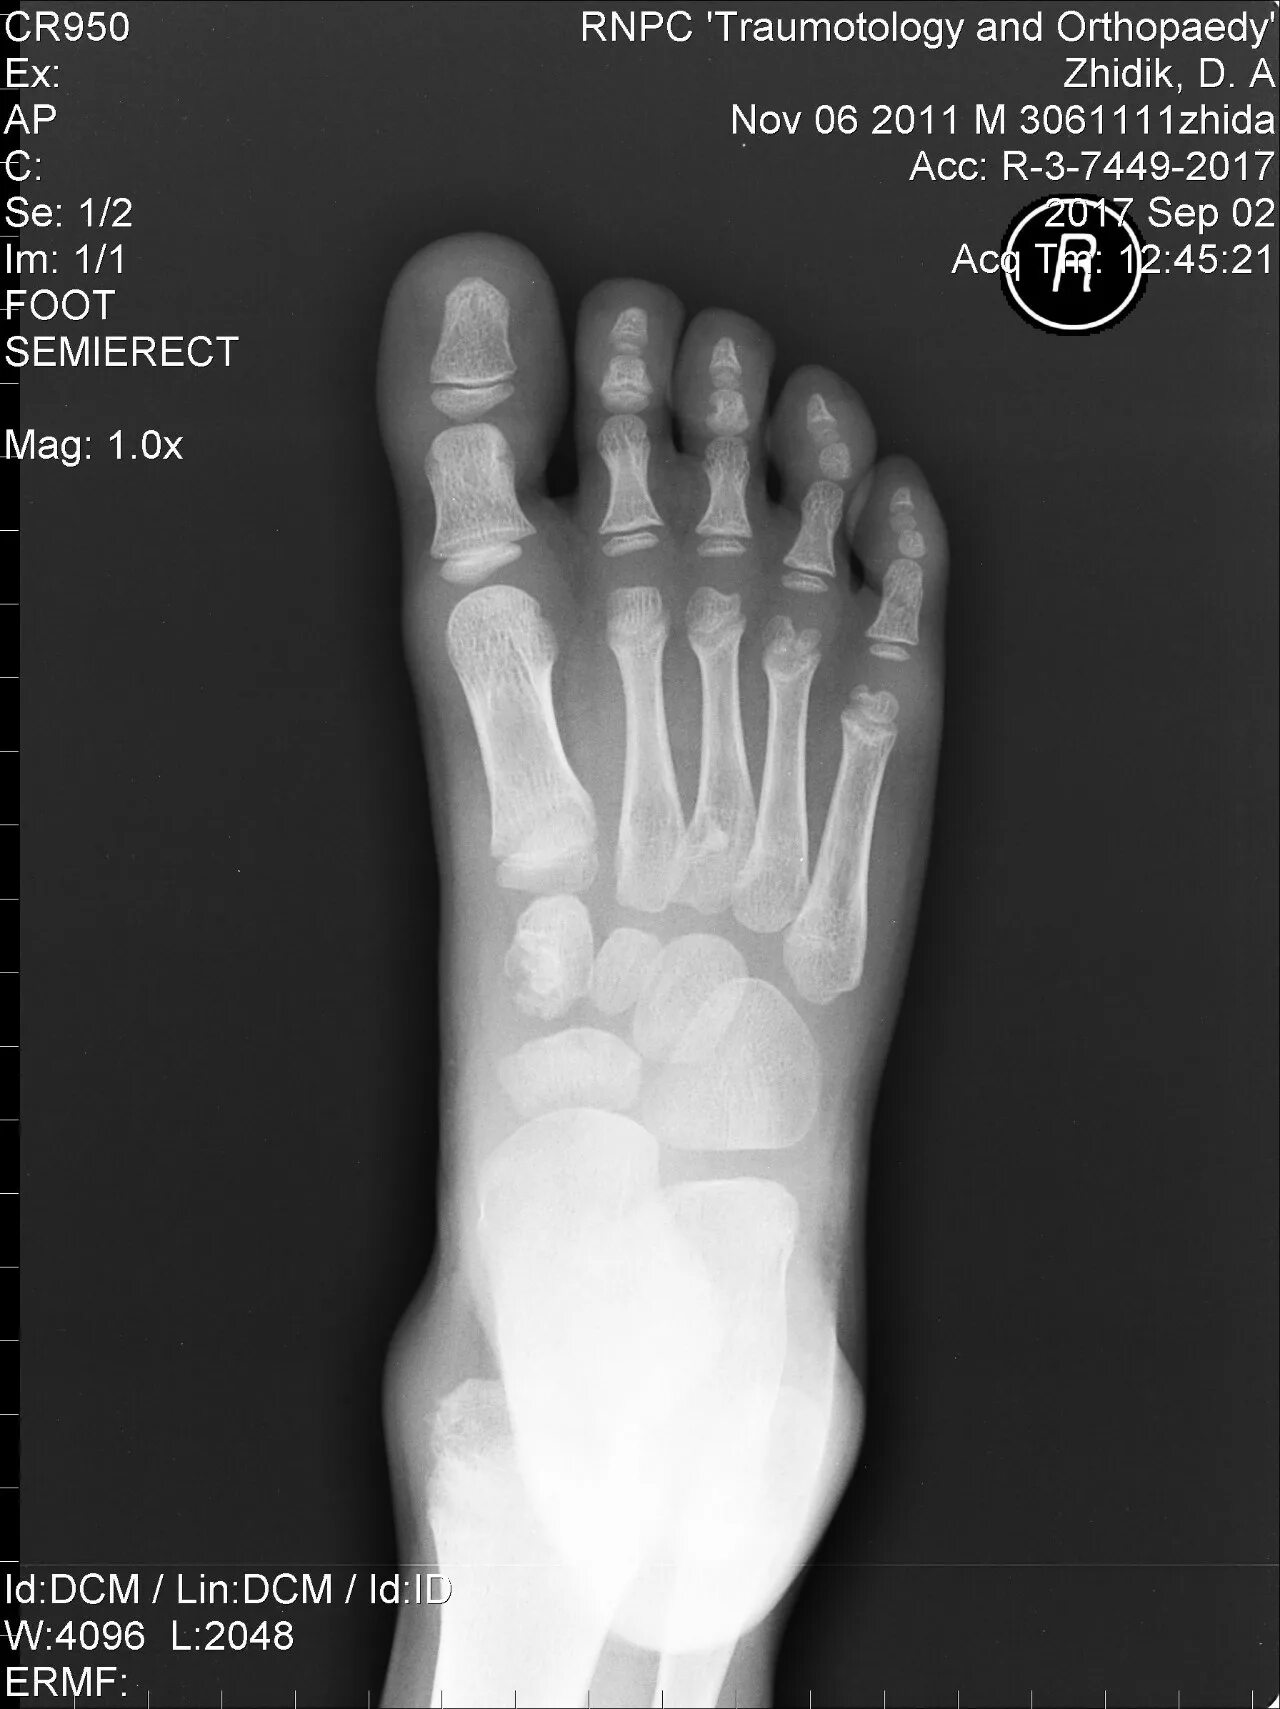

Келлера 3